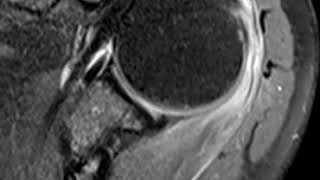

Flu vaccine tendinitis of shoulder video

Flu vaccine tendinitis of shoulder

Flu vaccine tendinitis of shoulder